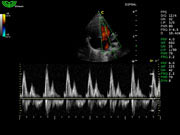

Система поддерживает СFM-режим, PW-режим, CW-режим, режим направленного энергетического потока, режим Color-M, панорамный режим, ECG, DICOM 3.0 и универсальные пакеты программ для кардиологии, сосудистого исследования и акушерства.

Режимы изображения: B, 2B, B/M, B/BC, CFM, PW, HPRF, PD, направленный PD, CW, режим Color M.

Дополнительные возможности: триплекс, трапециидальное отображение, анатомический М-режим, «free-hand» трехмерная реконструкция, авто-доплер.

D3P64L 3.0МГц, фазированная решетка.

2.0МГц – 4.4МГц. Применения: кардиология, брюшная полость, акушерство. |